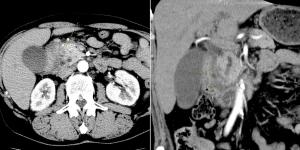

A 56-year-old woman presents with abdominal fullness and virilization. Axial and coronal images from a CT scan of her abdomen are shown below. What is your diagnosis?